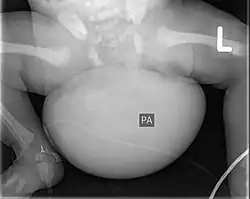

Das Steißbeinteratom oder Steißteratom (lat. teratoma sacrococcygeale), ein Teratom im Bereich des Steißbeins, ist die häufigste Manifestation von Keimzelltumoren des Kleinkindalters. Es bezeichnet einen Fehlbildungstumor im unteren Bereich der fetalen Wirbelsäule, der bis in das Becken des Ungeborenen vorwachsen kann.[1][2]

Dieser Tumor kann, durch die falsche Entfaltung der Keimblätter, alle möglichen Arten von Gewebe bis hin zu Organen oder weiteren Gliedmaßen beinhalten. In über 90 % der Fälle sind Steißbeinteratome gutartig, neigen jedoch dazu, bösartig zu werden. Bis zur Geburt können sie bereits kindskopfgroß sein. Eine Untergruppe der Tumoren wird so stark durchblutet, dass hierdurch ein schweres fetales Herzversagen bis hin zum Versterben des Ungeborenen auftreten kann.

- Fetal, bereits im Mutterleib, durch Ultraschall während einer Routineuntersuchung oder beim Feinultraschall

Zur Bildgebung kann der Tumor, dessen Struktur, Ausdehnung und Durchblutung gut im Ultraschall sowie in der Kernspintomographie dargestellt werden, im Röntgenbild können Kalk- und Knochenanteile sichtbar werden.[4]